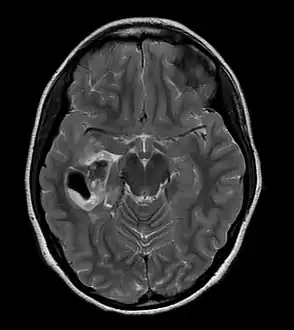

CT scan of a brain with pleomorphic xanthoastrocytoma. The classic radiographic appearance is one of a superficially situated tumor, here a mural nodule, associated with an underlying cyst.

• A CT scan of the brain, and/or an MRI scan of the brain and spine, will be performed. A special dye may be injected into a vein before these scans to provide contrast and make tumors easier to see.